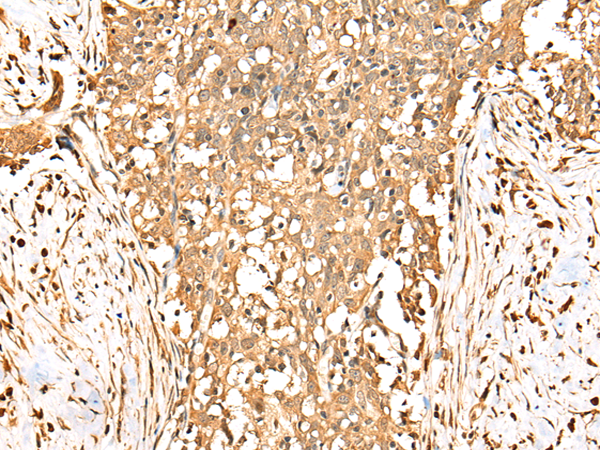

IHC positive control:  |

Human breast cancer and human esophagus cancer  |